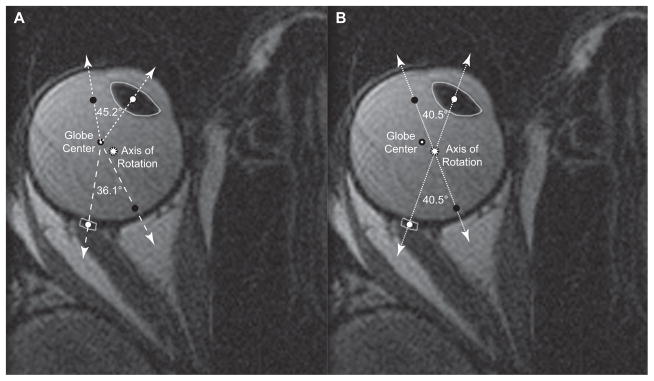

Fig. 2.

Two copies of the same axial magnetic resonance image of a normal right eye in adduction, but differently labeled according to rotational axis location. White dots represent centers of the lens and the globe-optic nerve (ON) junction in this gaze position, while black dots represent where the centers of the lens and the globe-ON junction were in central gaze. A. When adduction is assumed about globe center, the lens appears to rotate more (45.2°) than the globe-ON junction (36.1°), implying that the ocular rotational axis must be eccentric. B. The true axis of rotation, defined by the intersection of the lines between the lens center and globe-ON junction center in the different gaze positions, was offset medially more than 2 mm and posteriorly almost 1 mm from the geometric globe center. By definition, both lens and globe-ON junction rotated the same angle (40.5°) around the true rotational axis.

The foregoing differences imply that the globe does not rotate about its geometric center, but about a different rotational center for which computed rotations for every part of the eye are indeed equal. The intersection of lines connecting the lens center and globe-ON junction in central gaze and in eccentric gaze occurred at the true globe rotational center and represent the point about which the lens and globe-ON junction appeared to have equal rotational change (Fig. 2). Table 2 summarizes the average displacements of the true globe rotational axis from geometric globe center for each of the different gaze positons studied. Overall, globe rotational axis was eccentric by 2.2±0.5 mm medial and 0.8±1.0 mm posterior to geometric globe center during horizontal gaze changes and was displaced farther medially and posteriorly during adduction than abduction. There was minimal correlation between the magnitude of the eccentricity of the axis of rotation and axial length.